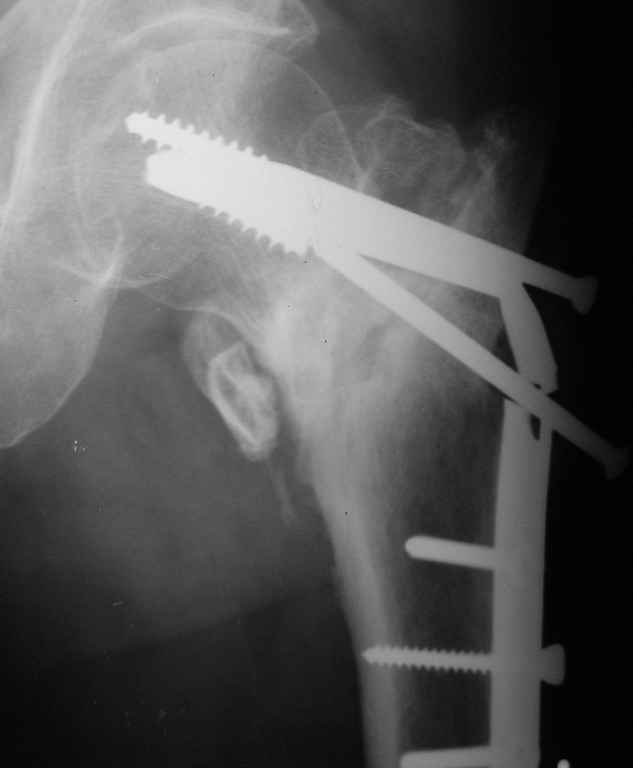

Сломанный спонгиозный винт, как достать??

Уважаемые коллеги!Подскажите пожалуйста, кто как и чем удаляет сломанные спонгиозные винты из шейки и головки бедра.